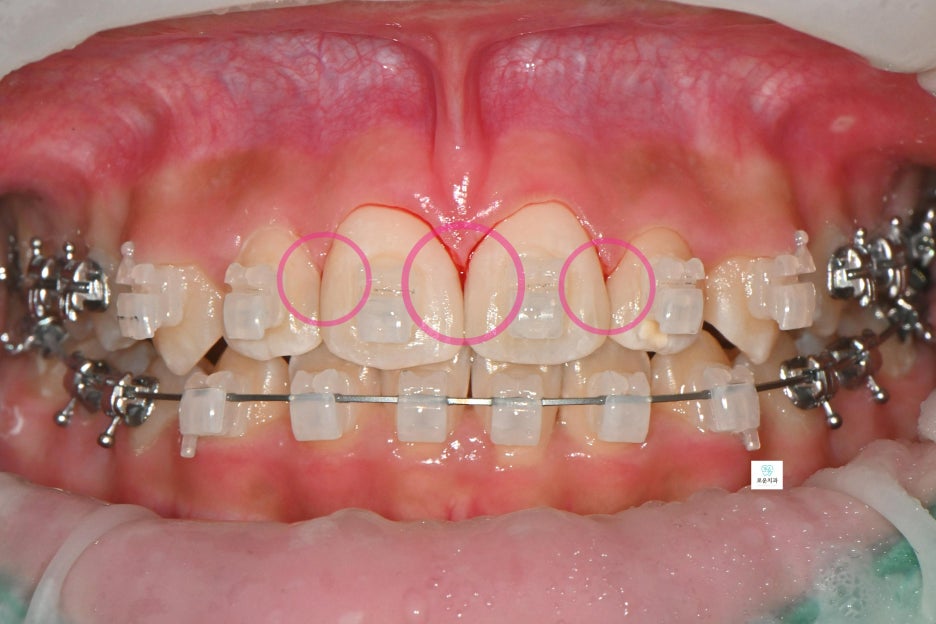

“교정 중 발생한 앞니 사이 충치 치료 사례”

장기간 교정 치료를 진행 중이던 환자분으로

앞니 사이 충치가 발견되어 치료를 위해

내원하셨습니다.

앞니에 생긴 우식은 치아 4개에 사이에 생겨 총 6면의 우식이 발생

→ 치아는 붙어 있는 면 양쪽으로 우식 진행되기 때문에 면수로 진행

첫 방문에서는 검진을 통해

치료 부위를 확인하였고,

두 번째 방문에서는 교정치과와 일정 조율 후

와이어를 제거한 상태로 내원하여

치료를 진행했습니다.